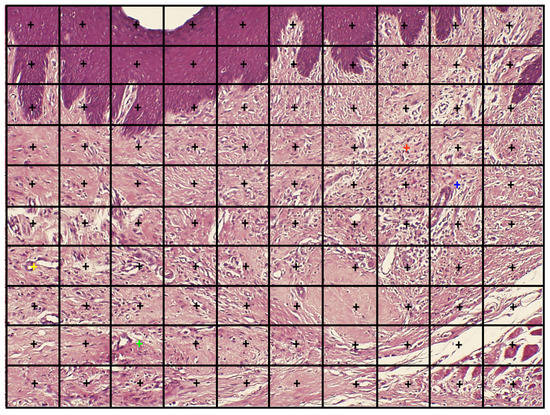

Histomorphometry (Inflammatory Infiltration, Vascular Density)

Histomorphometry (light microscope, Olympus BH-2, Tokyo, Japan) was performed on a transversal plane of the maxilla. The histomorphometric method was an adaptation of the point-counting procedure [30]. In practice, selected fields were photomicrographed (JPEG format) at ×100 using a camera (Olympus DP70, Tokyo, Japan) with the wound area being positioned in the center of the field and the surface epithelium being positioned at and in parallel to the upper photographed field. Then, the JPEG photomicrograph was transported to a full PPT slide dimension. A 10 × 10 square-grid overlapped on top of each PPT slide. Point counting was performed on inflammatory infiltration and vascular density. Whenever the graticule-square center (marked by a "+") hit the parameter, it scored one point (Figure 4). The sum of points of the parameter in each case (Pi) was calculated and expressed as the area fraction percentage (AFP) as part of the total number of "+" summed in all sections that represent the whole section area (Σi) [31,32]. The results were represented as mean AFP for inflammatory infiltration and vascular density in each group.

Figure 4. An example of the point-counting method. The "+" overlying the oral lining epithelium at the top of the photomicrograph should be excluded from counting. The yellow "+" overlies a blood vessel, therefore this parameter will be attributed 1 point. The green "+" is only adjacent to a blood vessel, therefore this parameter will score 0 points for the blood vessels. The orange "+" overlies an inflammatory cell (gain of 1 point), the blue "+" is only adjacent to inflammatory cells (0 points) (H&E, original magnification ×100).